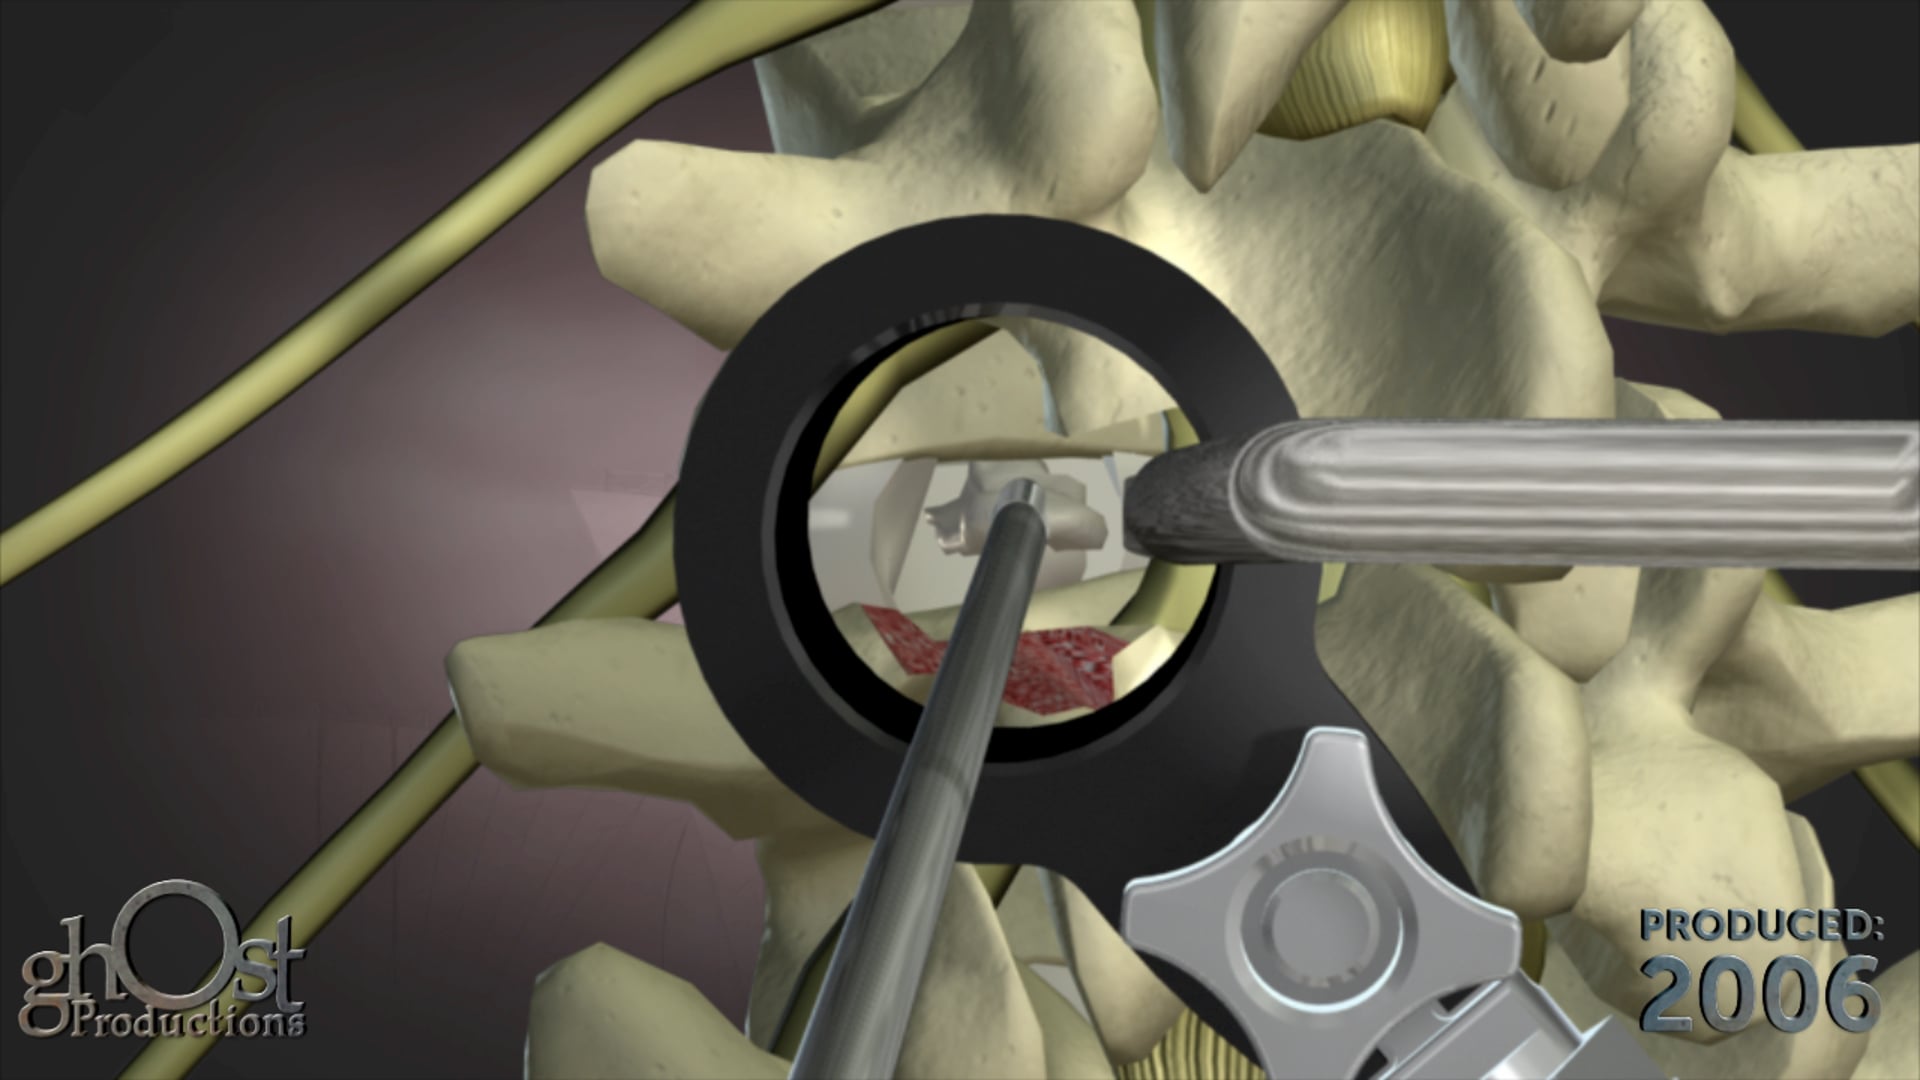

Expanding Orthopedics partners with Ghost Productions to create an animation showcasing their VCF posterior lumbar fixation system for spinal stabilization.

Expanding Orthopedics has collaborated with Ghost Productions to create an informative animation showcasing their VCF posterior lumbar fixation system. This innovative device is designed to stabilize spinal motion and promote interbody bone fusion in patients suffering from vertebral compression fractures. The animation demonstrates how the threaded interbody fusion cage is inserted into the lumbar disc space and used in conjunction with standard pedicle screws to provide optimal support and healing. This video is a valuable resource for medical professionals seeking to learn more about this cutting-edge technology in the field of orthopedics.